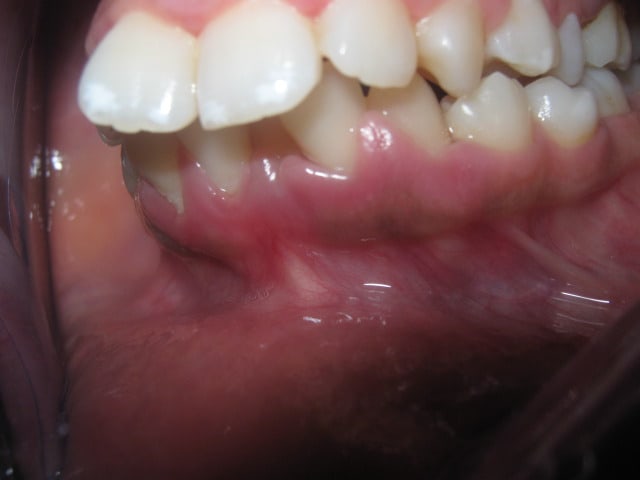

17/06/2011 à 13h45

on a fait des TP pour l arc utilitaire de ricketts

la patiente a un sourire gingival comment voulez vous que je n'ingresse pas ses incives

pour ça j'ai utilisé un 16 NITI courbe de spee inversé

Img 1461 nwsssd - Eugenol

Personne n'a contredit le besoin de faire une ingression, mais est-ce que tu connais bien les regles d'or pour faire une bonne ingression des incisivies?

1- Il faut corriger l'axe avant de faire l'ingression, cela fait partie de la regle TVA à ne pas manquer!

2- Pour faire de l'ingression pure il faut un arc de base obligatoirement, ou similaire.

3- Pour faire un arc de base superieure il faut savoire quel fil et quelle section, en bas et en haut

4- Pour faire un bon arc de base d'ingression il faut repondre à 12 questions en ce qui concerne les informations à donner à l'arc avec les reponses oui, non combien et pourquoi. Est-ce que tu t'es posé ces questions??

5- Si ton instructeur ne fait pas la technique de Ricketts dans son cabinet et ne maitrise pas parfaitement cette phylosophie il sera incapable de te l'enseigner correctement, avec tout le respect à tes profs.

> pour ça j'ai utilisé un 16 NITI courbe de spee inversé

Ce système provoque obligatoirement une egression des secteurs lateraux!! 0.5 mm d'egression laterale annule l'avantage de 2 mm d'ingression incisive!!! est-ce que tu le sais bien???

Une derniere remarque, pour bien documenter tes cas il faut investir dans du materiel photo de qualité acceptable et faire des moulages plus professionnels, cela montre l'etat d'esprit du praticien.